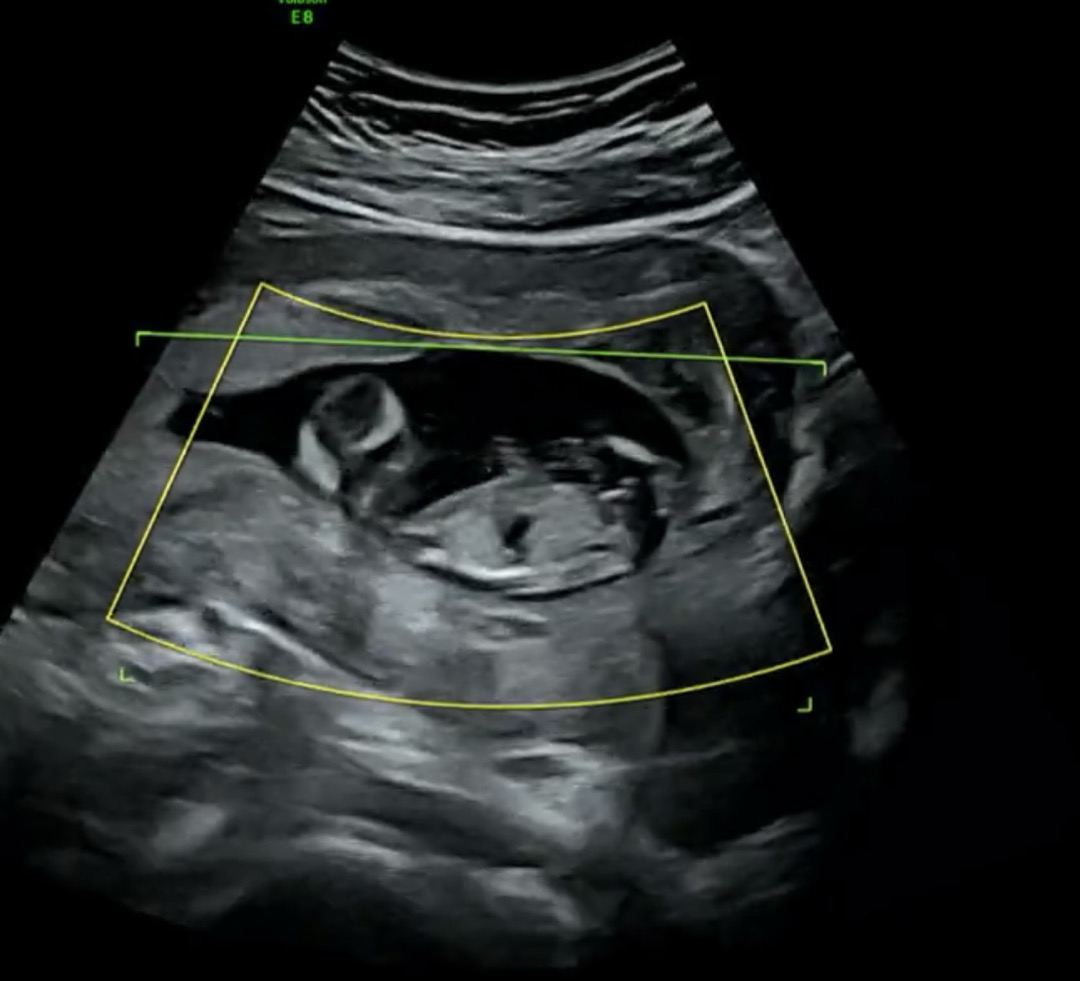

각도법 봐주실 고수분들 계실까요?

각도법 제발 봐주십시오 !! 🙏🏻🙏🏻🙏🏻